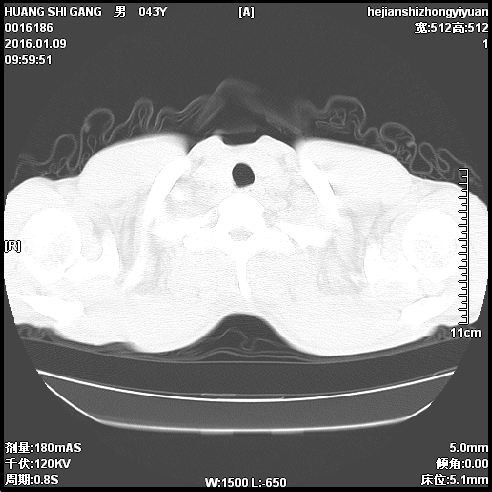

CT51513:左肺下叶小结节

患者胸疼多日

左下肺良性结节可能大,建议随访

多考虑血管畸形排除支扩并连夜栓塞

多考虑血管畸形

左下肺良性结节可能性大,建议随访

倾向于良性结节,建议随访